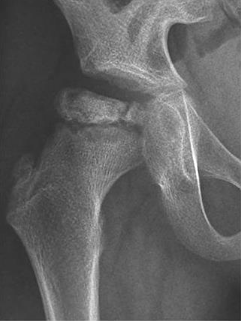

图三:碎裂期X线表现,可见患侧股骨头骺出现1条或以上纵裂

2.碎裂期:病理上为血运修复/重建期。在缺血/坏死期,股骨头骺虽缺血然而形态尚变化不显。随着血运逐渐恢复,破骨活跃,坏死骨被破骨细胞清理并代之以纤维组织、无成骨活动。碎裂期股骨头的强度变弱,在过载(负重)下逐渐塌陷变形。此期患儿行走跛行、髋关节疼痛等临床症状最显著,炎症相关指标处于最高水平。结合股骨头变形相关因素分析,在护理时,需强调较严格免负重,避免对于力学脆弱的股骨头施加过大的载荷。此期常持续6~12个月。